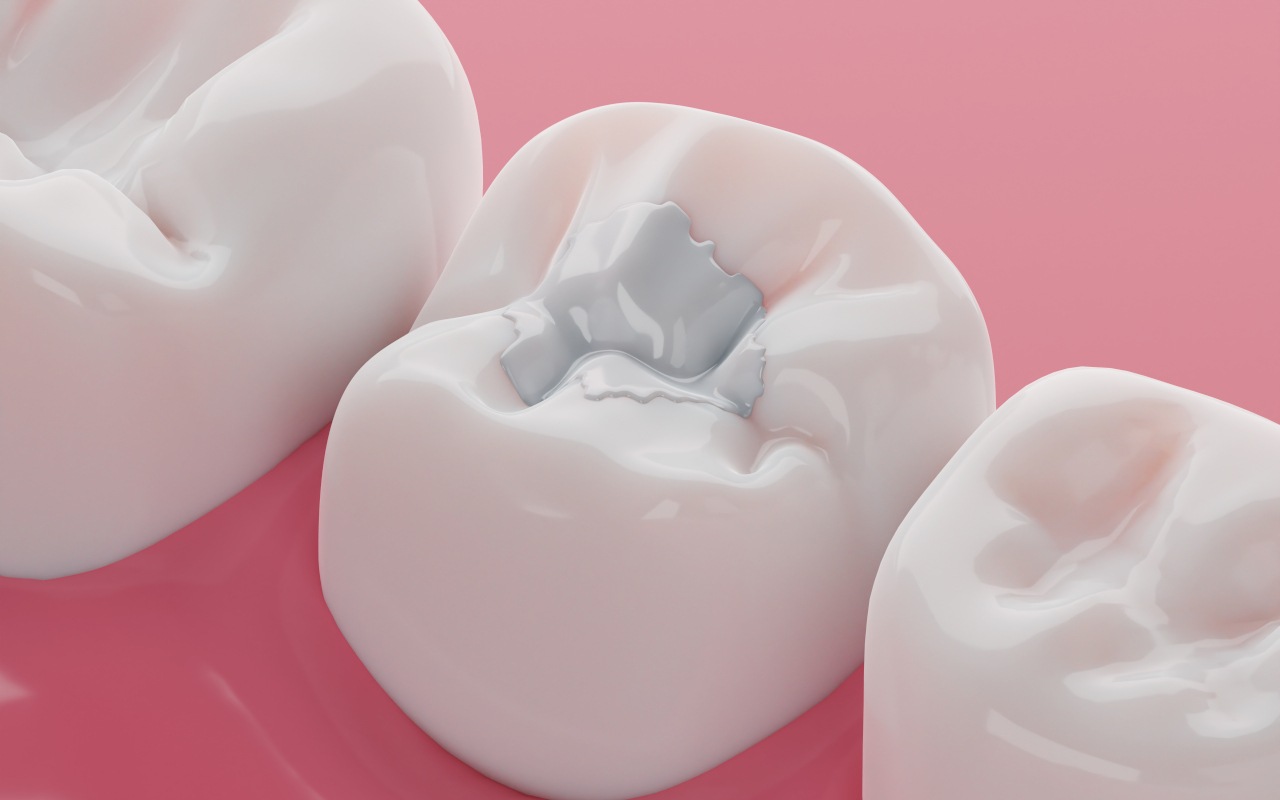

| ZahnerhaltFüllungen – zahnschonend und minimalinvasivParodontosebehandlung: Individuell abgestimmte moderne Behandlungsverfahren um die Erkrankung des Zahnhalteapparates zu kontrollieren Wurzelkanalbehandlung: Maschinelle Aufbereitung des Wurzelkanals mit elektrischer Längenmessung |

| ÄsthetikBleachingästhetische Frontzahnversorgungen (Füllungen, Veneers, Kronen) ICON Behandlung |

| KinderzahnheilkundeFrüherkennungsuntersuchungVorsorge Milchzahnfüllungen Mundhygieneunterweisung Ernährungsberatung |